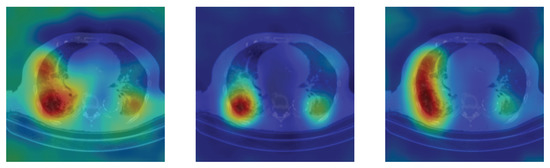

4.5. Heat Map

To have more intuition about the most important lung regions that the CNN architectures consider to classify the slice images, we used the randomized input sampling for explanations (RISE) approach [37]. Figure 13, Figure 14 and Figure 15 consist of two heat map examples of COVID-19, Cap, and normal cases, respectively. In the first example from Figure 13, we notice that despite the lung segmentation being not fully correct (it misses a considerable part of the infected region), the four CNN architectures gave more importance to the infected regions and to the lung regions in general. In the second example from Figure 13, we observe that the lung lobes were precisely segmented, and the heat maps of the four CNN architectures were well defined the infected regions, especially the Wide-Resnet-50 architecture. From both Cap examples in Figure 14, we notice that despite the lung segmentation missing considerable infected parts as well as the lung lobe regions, the heat maps of all CNN architectures give more importance to the infected region and to the lung lobes in general. This proves that the trained CNN architecture is able to define the regions of interest even when the lung lobes segmentation is not good. For the normal slice examples in Figure 15, the trained CNN architectures gave more importance to the lung lobes, especially the lower region, since the infection usually occurs there. The heat maps of COVID-19, Cap, and normal cases prove that the CNN architectures learned precisely where to look to identify the infection from the slice images.

Figure 15.

RISE heat map examples of normal slice image using the trained multi-tasks CNN architectures (ResneXt-50, Densenet-161, Inception-v3, and Wide-Resnet-50). The first example is shown in the first two rows, where the images represent the input slice image and segmented lung lobes results, followed by the heat maps of ResneXt-50, Densenet-161, Inception-v3, and Wide-Resnet-50, respectively. The second example is in rows 3 and 4.